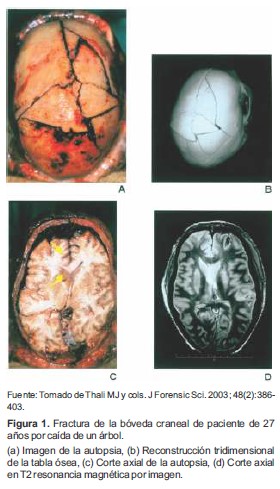

A. Fractura de la bóveda craneal

La RM, por mérito propio, es la mejor técnica para observar el sistema nervioso central. Ofrece imágenes únicas de todo el contorno del encéfalo; y a su vez, haciendo uso de las múltiples secuencias de contraste, permite realzar la protuberancia, el líquido cefalorraquídeo y la totalidad de la morfo fisiología cerebral (32-34).

Gracias a la RM se observa en detalle efluvios y sangrados en regiones centralizadas, como el hipocampo, el cuerpo calloso y los plexos coroideos; sirviendo también en la identificación de traumas junto a hemorragias subdurales y subaracnoideos, así como en probables daños en el sistema ventricular (35). Por lo anterior es la herramienta idónea a usar en pacientes que han fallecido por poli-traumatismos en accidente de tránsito, por golpes con objetos contundentes o caídas desde grandes alturas, también, claro está, para observar la complejidad del daño y los factores que causaron su muerte (36) (Figura 1).

No sobra recalcar, que esta técnica no sustituye del todo la autopsia convencional (Figura 1a), pero sí, es una poderosa herramienta para visualizar elementos omitidos por el estudio humano; permitiendo reconstrucciones tridimensionales o cortes axiales, donde sea fácilmente observable la posición y el tamaño de la lesión (Figura 1b y 1d); mejora además la comprensión de masas circunscritas de la cavidad que la contiene normalmente, por un orificio natural o accidental (flechas amarillas en la Figura 1c), lo que equivale a determinar magnitudes físicas, como distancias, tipo de objetos, entre otros.

Figura 1. Fractura de la bóveda craneal de paciente de 27 años por caída de un árbol.

(a)Imagen de la autopsia, (b)Reconstrucción tridimensional de la tabla ósea, (c)Corte axial de la autopsia, (d)Corte axial en T2 resonancia magnética por imagen.